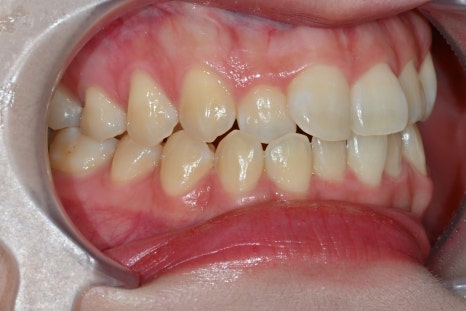

The key to naturalness: translucency

Laminate is not determined by color,

but by “translucency.”

In this case as well,

the central front teeth were given a natural color tone, while the surrounding teeth were adjusted for translucency to create an overall harmonious result.

Seoul Ob Dental Hospital

has a strength in expressing this translucency.